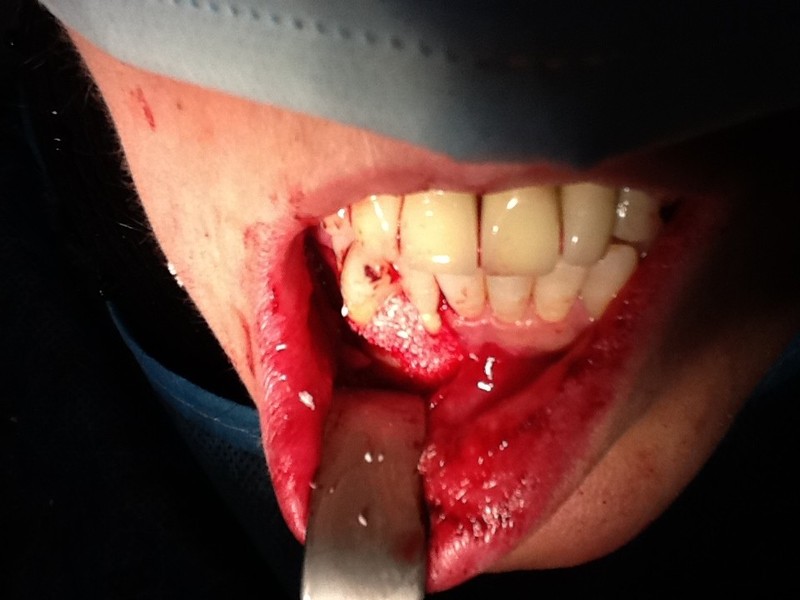

Chirurgia plastica Muco-Gengivale

Rigenerazione Gravi difetti parodontali